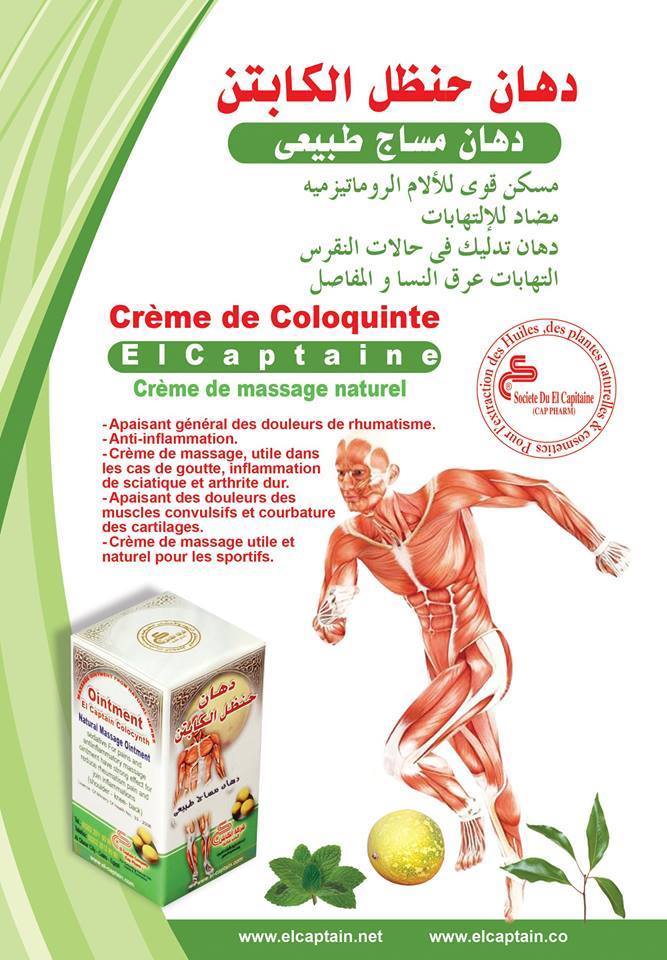

12 pcs Captain Colocynth Balm Muscle Pain Relief Herbal Ointment 12 pcs x 50mg

12 pcs Ointment El captain Colocynth Handal Herbal Muscle Pain Massage Relief Weight: 50 gm= ( 1.76 oz ) - Material: The Fresh Colocynth - Eucalyptus Globulus - Cumin Extract - Gaultheria - Fennel Extract - Eugenol - Natural Mint Extract - Carvhon Limonin Sedative For Pains Ointment Has Strong Effect , Suitable for reducing muscle pain, joint pain, back pain and soft tissue After the ointment has been applied, muscles will relax. Also recommended to be used as a sports ointment. Ideally suited to people who engage in rehabilitative sports. Production and expiration dates are indicated on the original packaging in the European format MM/YY